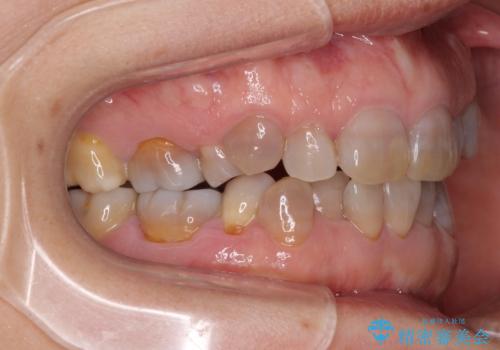

- 小さいころからの歯の変色と矯正治療の後戻りを気にして来院された患者様です。

気になる変色歯を仮歯に変え、その後歯列不正を矯正治療で改善し、最後にオールセラミッククラウンにて補綴治療することとしました。